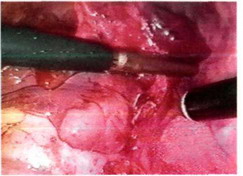

Рис. 26-5. Выделение нижнедолевой артерии.